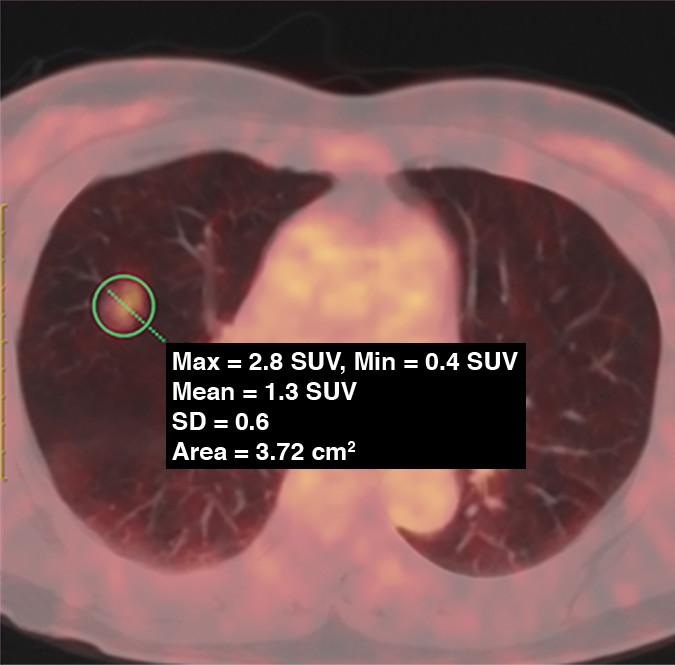

image: 62-year-old woman with pure GGN. PET/CT fusion image shows pure GGN with tumor maximum standardized uptake value (SUVmax) of 2.8 (circle).

Shao and colleagues' retrospective analysis was conducted on the PET/CT data on ground-glass nodules (GGNs) resected from patients with stage IA lung adenocarcinoma, evaluating the efficacy of PET maximum standardized uptake value (SUVmax) combined with HRCT signs in prediction of histopathologic subtype and growth pattern of lung adenocarcinoma.

Although SUVmax measured significantly higher in GGNs with invasive HRCT signs, the diameter of GGN, as well as the attenuation value differential between ground-glass components and adjacent lung tissues, were independent predictors of FDG uptake by GGNs.

Additionally, SUVmax was higher in invasive adenocarcinoma than in adenocarcinoma in situ (AIS)-minimally invasive adenocarcinoma (MIA), with SUVmax 2.0 the optimal cutoff value for differentiation.

Acinar-papillary adenocarcinoma had a higher SUVmax than lepidic adenocarcinoma, with SUVmax 1.4 the optimal cutoff value for differentiation.